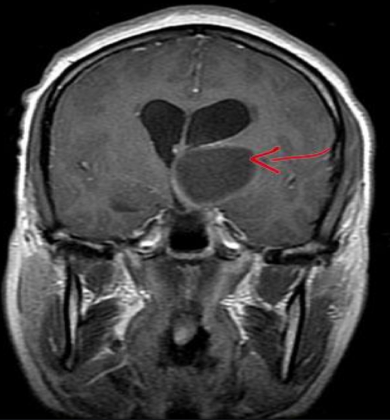

基底节胶质瘤:早期发现、及时治疗是存活的关键

基底节区 胶质瘤 ,是指生长在基底节区或附近的胶质瘤。基底节(basal ganglion)又称基底核(basal nucleus),位于近大脑半球底部的白质中,是大脑半球深部较大的核团,位于基底节区的胶质...